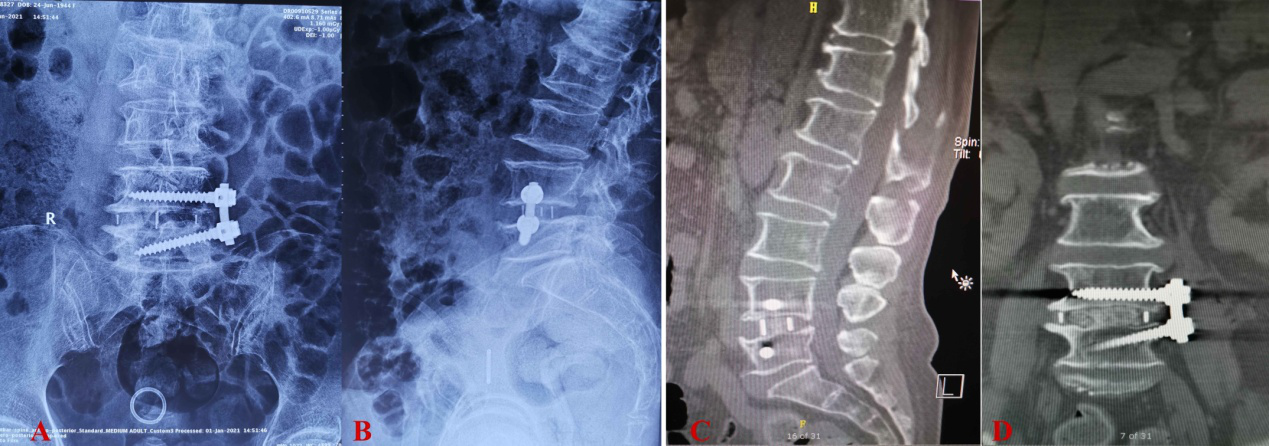

图1 患者术前部分影像学资料

(A,B:腰髓MRI T2相矢状位;C,D: 腰髓MRI T2相轴位-腰5/骶1水平;E:腰椎正位X平片; F:腹部CTA)

患者为76岁老年女性,因“间断性腰腿疼10年,右下肢麻木、无力并跛行3月,加重1月余”收入神经外科。入院诊断为:腰椎间盘突出伴坐骨神经痛、腰椎椎管狭窄症、脊柱侧弯畸形。患者主要体征为跛行,驼背明显,腰骶部压痛。右下肢近端肌力IV级,远端肌力III级。右足背伸、内翻、外翻力量弱,右侧踇趾及足趾背伸不能。患者入院后完善腰椎CT三维重建、腹主动脉CTA、肌电图、心脏彩超、肺功能等相关检查。患者年龄较大,同时存在神经根压迫症状及椎管狭窄症状,病情比较复杂。

斜外侧椎间融合术(OLIF)为2012在国外开始兴起的新术式,由于创伤性小、手术时间短、术中出血少的特点,在国外已常规开展,但山东省及绿帽社开展的数量还比较少。常规斜外侧椎间融合术适用于腰2-腰5退行性病变的患者,而腰5/骶1间隙由于受骨盆髂嵴阻挡及腹主动脉向两侧分叉的髂总动脉覆盖椎间隙的原因,手术显露非常困难。该例患者引起症状的责任间隙即为腰5/骶1,全脊柱X平片及三维重建CT等影像学检查提示该患者存在骶1椎体腰化变异(即该患者有六节腰椎,见图1),髂嵴对腰5/骶1间隙的阻挡并不太严重,从而使得OLIF术式成为可能。但患者腹主动脉CTA提示腹主动脉分叉较早,入路受髂动脉影响,仍然增加了手术难度、风险及不确定性。神经外科脊柱脊髓专业团队对患者症状、体征及术前影像充分分析和论证,考虑患者的高龄,最终确定了微创的OLIF术式为该患者的最佳治疗方案。